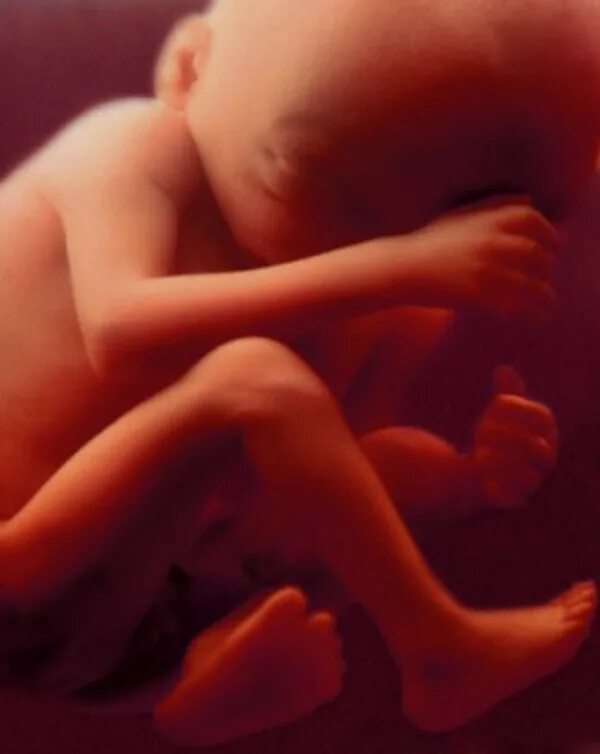

Плод на 31 неделе беременности. ребенок в животе 31 неделя.Эмбрион 31 неделя беременности. малыш на 31 неделе беременности.Плод на 31 неделе беременности. эмбрион 31 неделя беременности. малыш в утробе 31 неделя беременности.Малыш на 31 неделе беременности. малыш в животике 28 недель. малыш в утробе 31 неделя.Младенец в утробе. малыш в утробе 31 неделя. ребёнок на 31 неделе беременности.Плод на 31 неделе беременности. ребёнок на 31 неделе беременности. малыш в утробе 31 неделя. младенец на 31 неделе беременности.Плод на 31 неделе беременности. 30-31 неделя беременности. эмбрион 31 неделя беременности. 31 акушерская неделя беременности.Малыш на 31 неделе беременности.Плод на 31 неделе беременности. расположение ребёнка в утробе матери на 29 неделе.30-31 неделя беременности. ребёнок в матке на 31 неделе. плод на 31 неделе беременности.Плод ребенка. ребёнок на 31 неделе беременности.Плод на 31 неделе беременности. малыш в утробе 31 неделя беременности. ребёнок в 30 недель беременности. ркбкеок на 30 неделе беременности.Плод на 31 неделе беременности. малыш на 31 неделе беременности.Эмбрион леннарт нильсон. плод на 31 неделе беременности. леннарт нильсон фотографии.Малыш на 31 неделе беременности. ребёнок на 31 неделе беременности в животе. малыш в утробе 31 неделя беременности.Узи плода 31 неделя беременности. узи беременности 30-31 неделя. узи 31 неделя беременности мальчик. 31 неделя беременности узи фото.Узи на 33 неделе беременности мальчик. снимок узи на 31 неделе беременности. узи 31 неделя беременности мальчик.Плод на 31 неделе беременности. расположение ребенка в утробе матери на 30 недели беременности. расположение плода на 31 неделе беременности. малыш в утробе матери 31 неделя беременности.Узи плода 31 неделя беременности. 31 неделя беременности фото узи ребенка. снимок узи на 31 неделе беременности. узи беременности 30-31 неделя.Плод на 31 неделе беременности. 31 неделя беременности фото плода. плод ребенка в 31 неделю беременности. малыш на 31 неделе беременности.Плод на 30 неделе беременности. плод ребенка на 30 неделе беременности. ребёнок в 30 недель беременности. 31 неделя беременности фото плода.31 неделя беременности как выглядит31 неделя беременности фото плода на узи. 3д узи 31 неделя беременности девочка. 3д узи на 31 неделе беременности.Узи 31 неделя беременности. узи плода 31 неделя беременности. 31 неделя беременности узи фото. эмбрион на 30 неделе беременности узи.Ребёнок на 31 неделе беременности. узи хомиладорлик.Узи ребенка на 31 неделе беременности. 32 недели беременности фото плода на узи. 31 неделя беременности фото плода на узи. снимок узи 32 недели беременности.Малыш в животике на 32 неделе. ребёнок на 31 неделе беременности. 31-32 неделя беременности.Живот на 31 неделе беременности. животик на 31 неделе беременности. ребёнок на 31 неделе беременности в животе.Живот на 31 неделе. животик на 31 неделе беременности. беременный живот на 31 неделе.Беременность 29 недель положение плода. ребенок в животе на 25 неделе. плод на 32 неделе беременности. матка на 21 неделе беременности.Малыш в утробе 32 неделе беременности. плод 31-32 недели беременности. ребёнок на 32 неделе беременности в утробе. плод в 32 недели беременности в животе.Живот на 31 неделе. живот на 30-31 неделе. живот на 31 неделе беременности животик.Ребёнок на 24 неделе беременности. оебнок на 24 неделе беременности. новорожденный ребенок на 24 неделе беременности.Ребёнок 30 неделя беременности в утробе. малыш в утробе 31 неделя беременности.Ребенок в 32-33 недели беременности. плод на 33 неделе беременности. ребенок на 33 неделе беременности. малыш на 33 неделе беременности.Ребёнок в 34 недели беременности в утробе. 32 недели беременности фото плода. малыш в утробе 32 неделе беременности. ребёнок в 32 недели беременности в животе.Ребёнок на 32 неделе беременности. новорожденный в 35 недель.Малыш на 31 неделе беременности. новорожденный ребенок 31 неделя. рождение ребенка на 31 недели беременности.31 неделя беременности как выглядитПлод на 34 неделе беременности картинки. 34 неделя беременности фото плода. 34 эмбриональная неделя беременности. плод ребенка в 34 недели беременности.